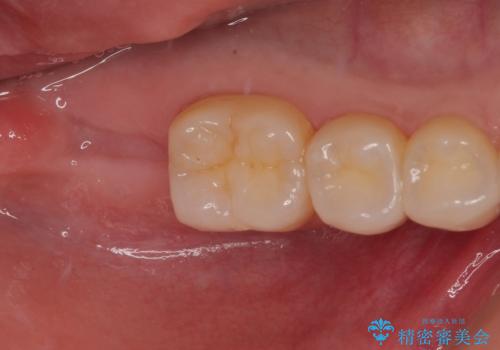

抜歯になった奥歯 速やかな埋入による短期間インプラント治療

- 奥歯が抜歯となり、インプラント治療を希望して来院された患者様です。

来院時には抜歯して1ヶ月ほど経過していたとのことで、3次元レントゲンよりインプラントの早期埋入が可能と診断されました。

インプラント埋入と同時に仮歯を装着するために、事前に仮歯を用意し、速やかにインプラント埋入を行うこととしました。